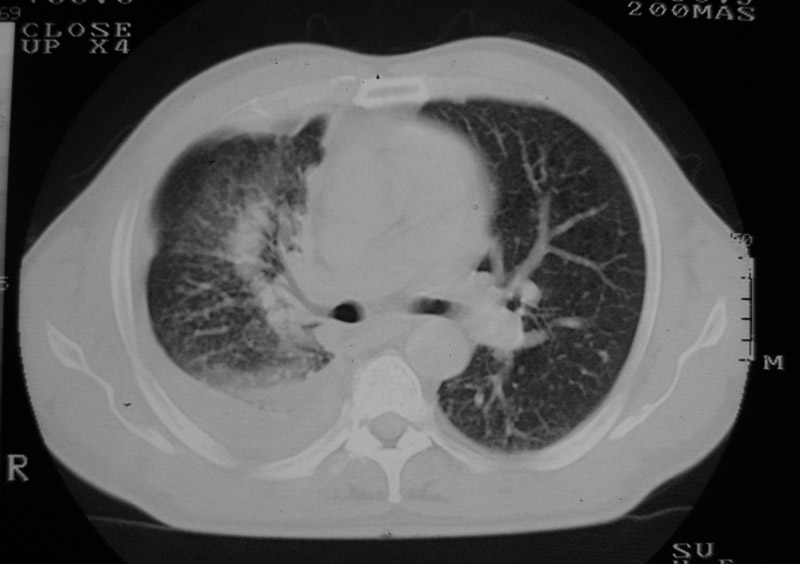

以下是引用守望可可西里在2006-9-11 15:29:00的发言:[br][br] ct平扫表现:右侧胸膜腔缩小,积液,胸膜增厚且不均匀、不规则,以纵隔胸膜增厚为主,边缘呈锯齿状,并见附壁内突之结节状肿块影。右肺含气量减少,纹理聚集,右肺门中下部见数个肿大的淋巴结。纵隔无移位,内未见明显肿大淋巴结,双侧主支气管以及各叶、段支气管比较通畅。。[br] 考虑:右侧胸膜恶性间皮瘤,伴肺门淋巴结转移。